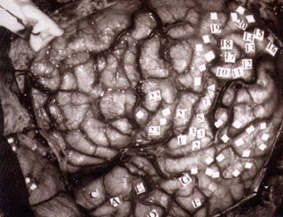

Figure 7. Human brain labeled as to cortical areas during neurosurgery

All of the progress described above is anatomical in nature. What about the function of the visual pathways? How were researchers approaching this issue in the late 1800s and early 1900s? Clinical cases described over the centuries already pointed to the functional specialization of discrete cortical areas. Experimental lesions within the cortex confirmed this notion. Electrical stimulation of the cortex (e.g. Hitzig and Fritsch on dog and monkey motor cortex) provided the coup de grace to the doctrine of functional equivalence and established the theory of functional cerebral localization in its place. Surgeons such as Penfield were mechanically stimulating the brains of conscious patients during operations and recording the sensations evoked (Fig. 7). The critical step in obtaining a functional map of the visual system, however, came when researchers moved from electrical stimulation to electrical recording.